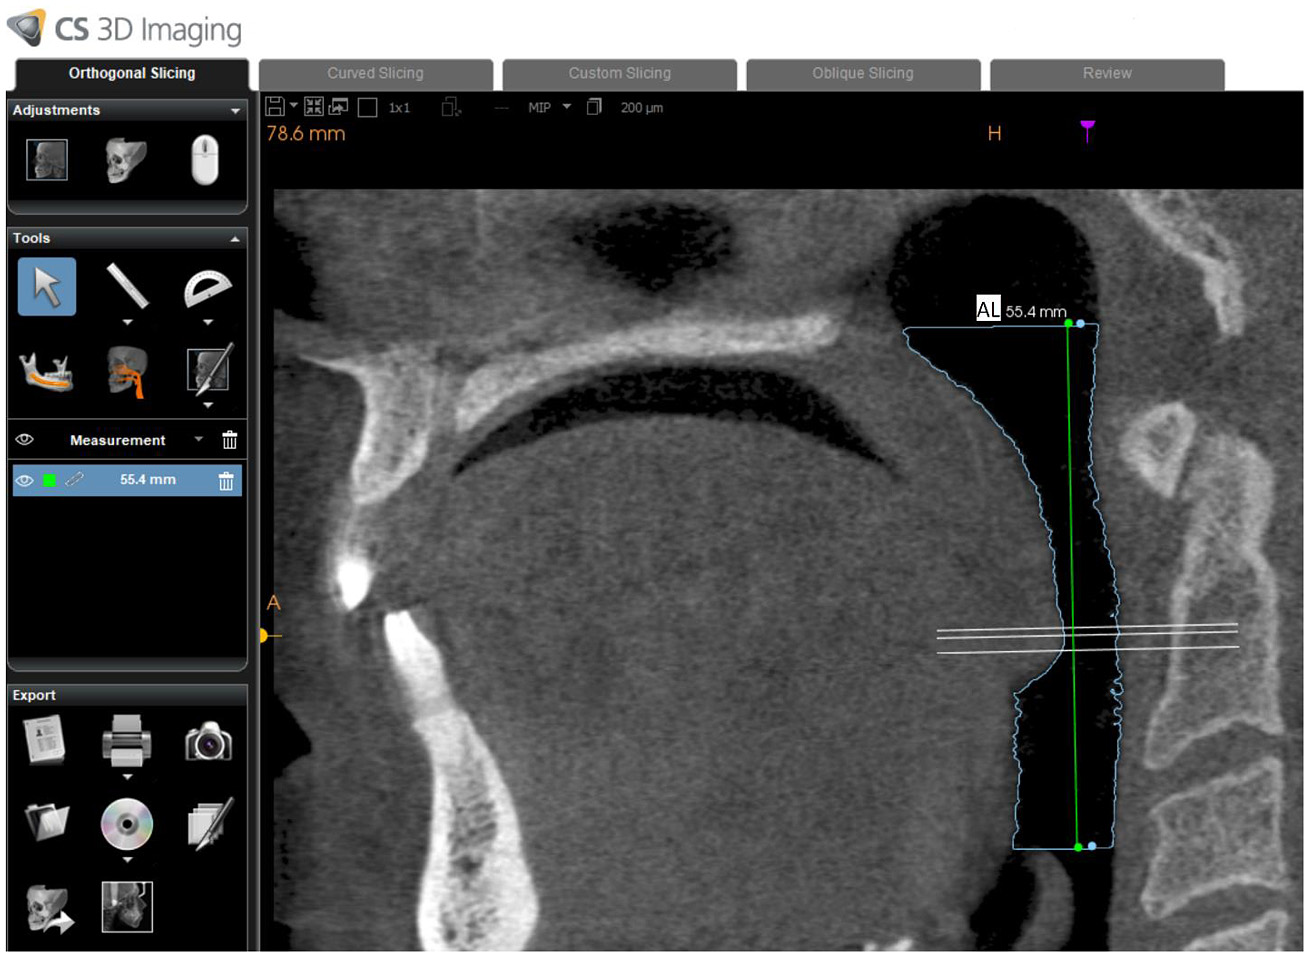

Using dedicated CBCT software (Kodak CS 3D imaging version 3.8.6, Carestream, Rochester, NY, USA), one calibrated oral radiologist (MA) with 12 years of experience with CBCT was responsible for drawing the path of the oropharyngeal airway from the posterior nasal spine to the superior border of the epiglottis on a midsagittal section (Fig. 1). The software subsequently and automatically generated the following values: airway volume (AV: cm3), minimum cross-sectional area (MCA: mm2), minimum anteroposterior distance (MAD: mm), and minimum right to left distance (MRD: mm). In addition to this, airway length (AL: mm) was manually measured by drawing a vertical line connecting the superior and inferior border of the oropharyngeal airway (Fig. 2).